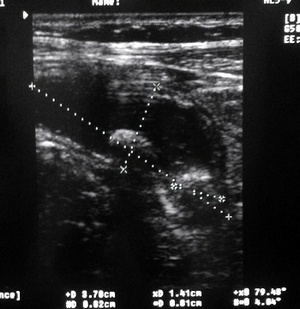

Загадка "на смекалку" :-) УЗИ, о.аппендицит

Как вы думаете, что это???

жидкостная тубулярная структура с конкрементами?

1. Воспаленный аппендикс, копролитами- фекалитами...

2.Жолчный пузырь...

но скорее первое, чем второе..

Serg, вы правы. п1-совершенно верно!!!

О.аппендицит с картиной о.холецистита )